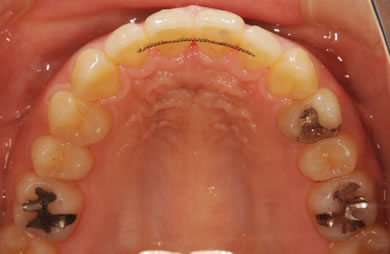

| 性別/年齢 | 女性 / 24歳 | ||||||||||||||||||||||||||||||||

| 治療方針 | 舌が横にはみでて、上下の歯が全く咬んでいない状態です。口元はきれいなので、歯は抜かずに歯列を少し横に広げて並べます。ゴムを使用したり、舌を訓練したりとても協力が必要な症例です。 | ||||||||||||||||||||||||||||||||

| 治療内容 | 唇側矯正(ホワイト)、保定装置 | ||||||||||||||||||||||||||||||||

| 治療期間 | 9ヶ月 |